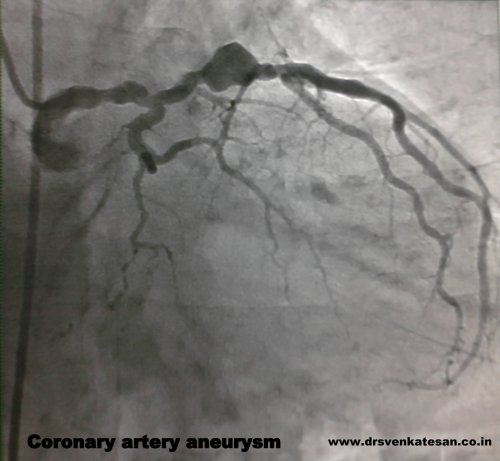

Here is a different facet of atherosclerosis , A middle aged man surprised us with this coronary angiogram . Instead of obstructing the flow the coronary vessel begins to dilate. This is due to a medial weakness .(The media for some reason begins to give way rather than proliferate to the atherogenic stimuli.)

One may wonder why he underwent CAG when obstruction is least expected in such a vessel ! It was paradox of sorts , this man in spite of his wide bore coronary artery , was prone for coronary thrombus and one such episode landed him in our CCU . ( Please note both faces of atherosclerosis “obstructive and dilatory” can manifest in the same vessel in different combination.)

This angiogram may be reported as any one of the following

- Diffuse atherosclerosis

- Diffuse atherosclerosis with focal dilatation and aneurysm formation

- Coronary ectasia